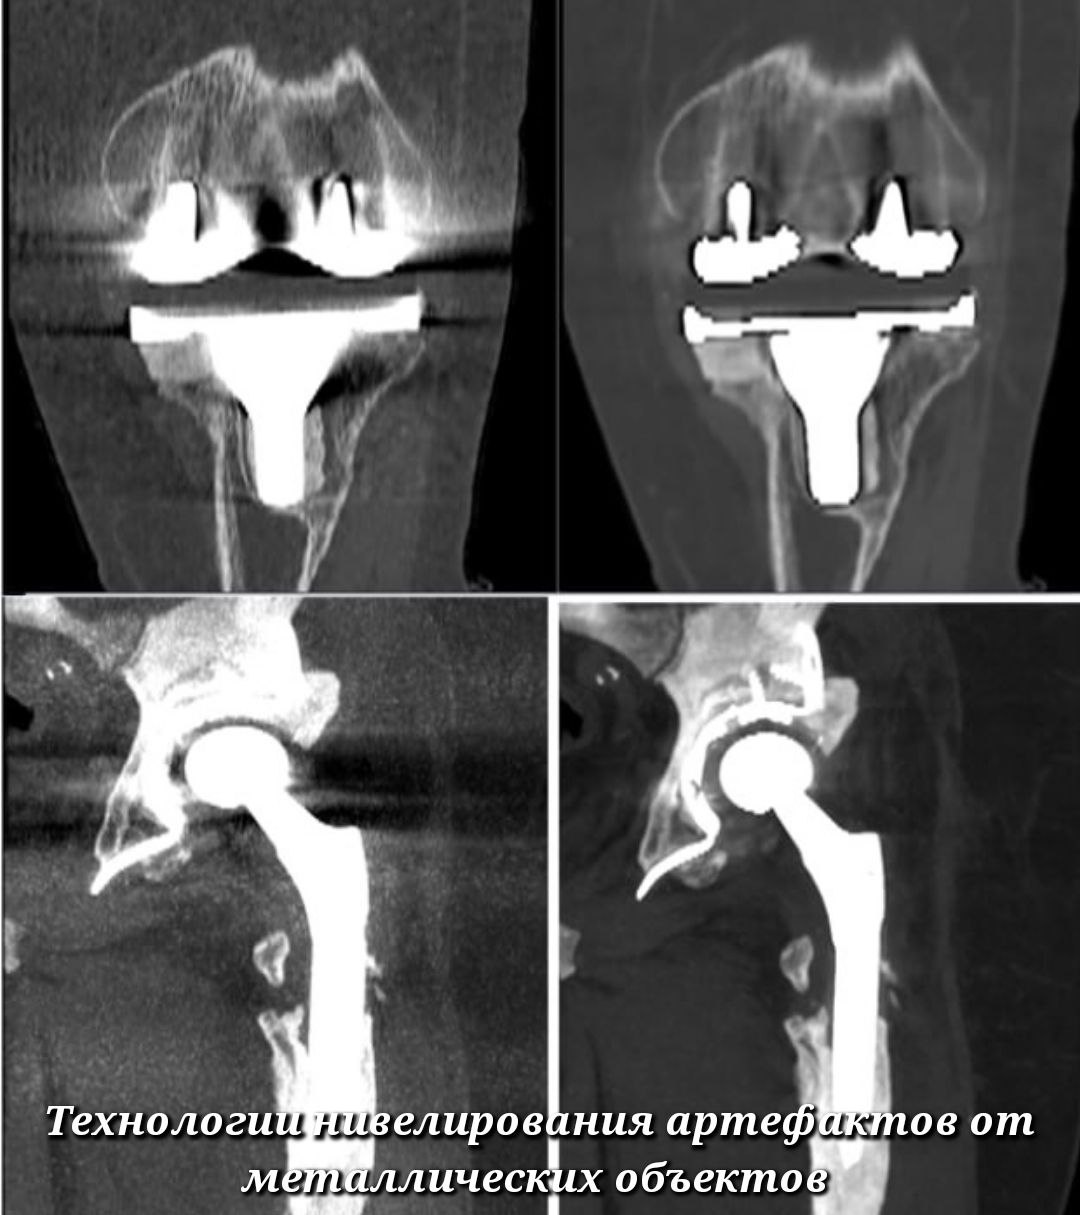

При исследованиях костно-мышечной системы рентгенологи травмбольницы увидят любое отклонение от нормы даже при наличии в организме металлических имплантатов - эндопротезов, пластин и т.д. Эти конструкции во время томографии дают сильное свечение или смазывают изображение. Такие проявления в диагностике называют артефактами. Они значительно затрудняют исследование. Но в клинике уже давно вооружились передовыми технологиями нивелирования артефактов и широко используют их в повседневной работе.